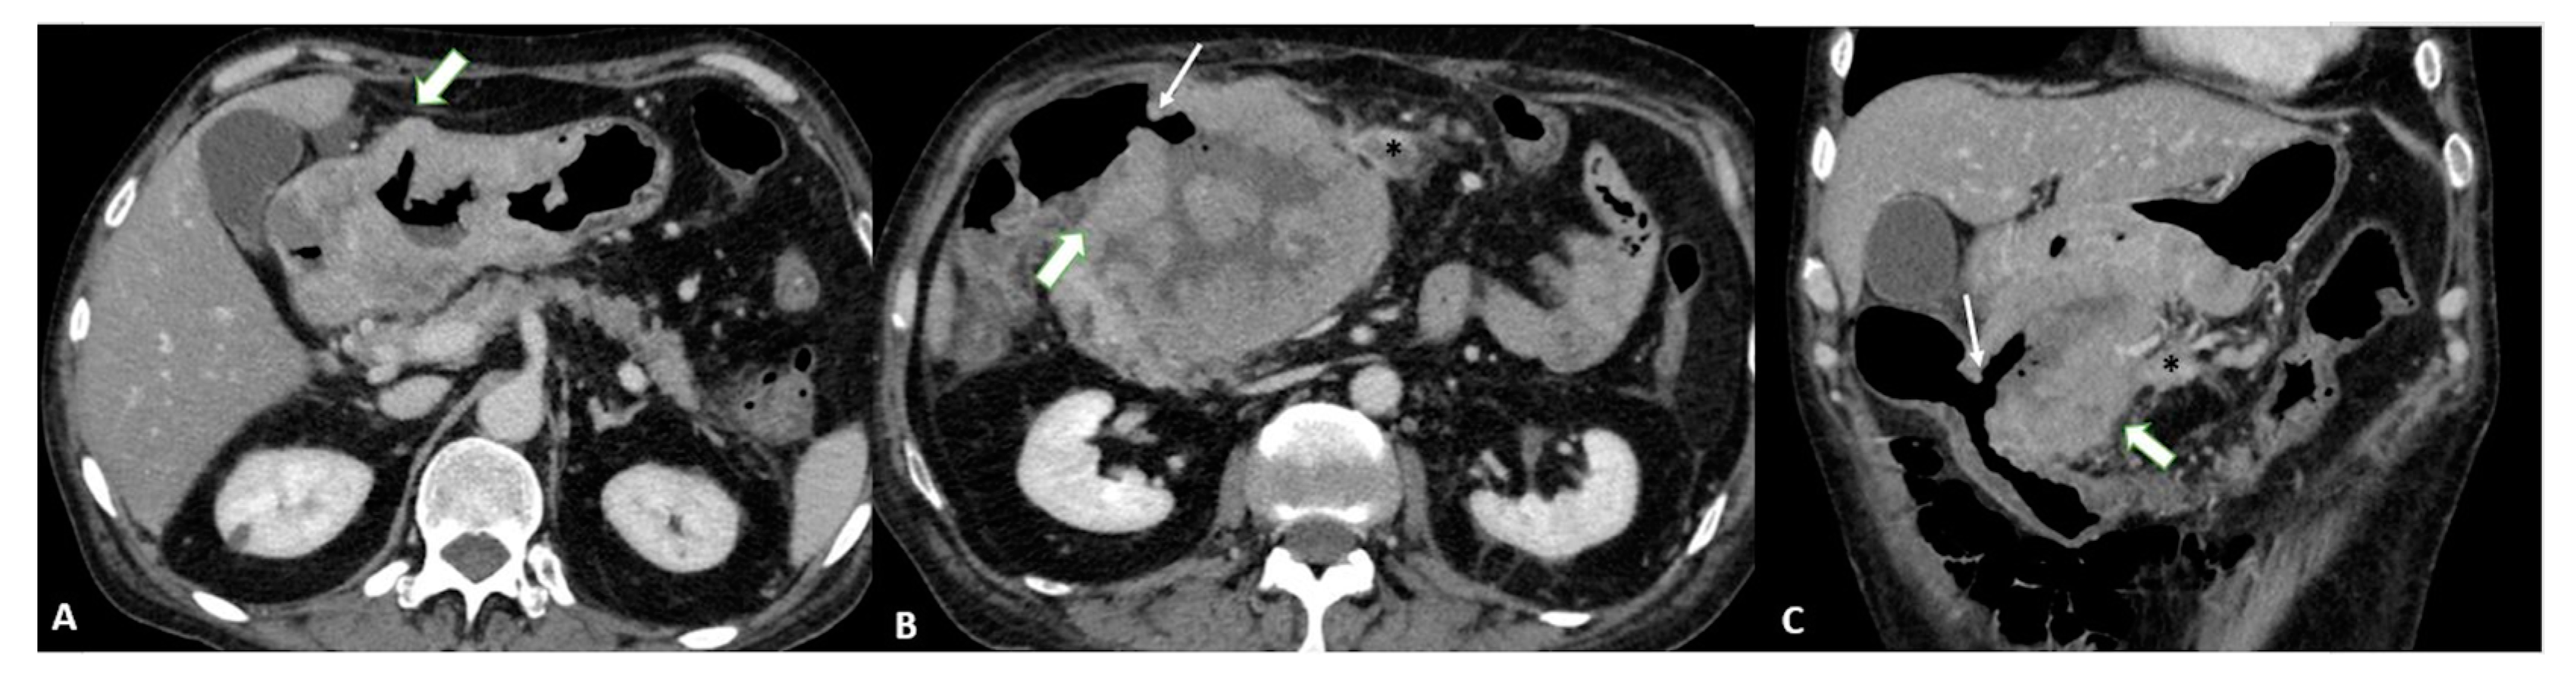

To distinguish normal from pathologic nodes, size is the most accepted parameter. However, there is no clear consensus on the threshold size for suspicious nodes. The threshold size depends on the location and ranges from 6 to 10 mm in the upper abdomen [34]. Other characteristics of metastatic nodes include a round shape, a cluster of more than three nodules, and the degree and heterogeneity of enhancement [35] (Figure 8).

Figure 8.

Axial 2D images in the portal venous phase show different pathological node locations (black asterisks): (A) pathological lymph nodes in the lesser curvature of the stomach; (B) pathological lymph nodes of the lesser curvature and the celiac artery; (C) pathological lymph nodes of the pancreatic head and para-aortic region. The lymph nodes in the images present an inhomogeneous contrast enhancement with central hypodensity due to the presence of necrotic components inside.

In addition, microscopic metastases can often be found in normal-sized nodes in patients with EGC, which reduces the accuracy of N staging in EGC compared with advanced cases [24].

According to a meta-analysis [10], the CT sensitivity and specificity of N staging range from 62.5 to 91.9% and 50.0 to 87.9%, respectively. These diagnostic values are associated with an acceptable accuracy level (86.3%), but the authors [36] highlighted an important problem with N-staging based on the mediocre to good inter-reader reliability (κ 0.449–0.662) in classifying the nodal status.

Nodal staging with MPR showed no significant improvement [23], with overall accuracy levels of 62% and 64% for axial images and MPR, respectively.